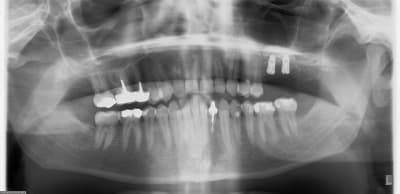

C'est une technique que je pratique très souvent et qui me donne entière satisfaction. Pour ceux qui se demandent à quoi cela ressemble, je poste un exemple.

Dans la littérature il n'y a pas vraiment d'étude RCT analysant juste cette technique chirurgicale. Cependant cette approche est largement utilisée dans les études sur les sinus lift réalisées par l'équipe de Stefan Lundgren & Lasse Sennerby en Suède, l'équipe de Ferrari Marco en Italie et celle de Sohn en Corée.

Je n'ai à ce jour eu aucune complication dûe à une nécrose du volet osseux (risque évoqué par Mac).

Merci Olivier de ta réponse sans ambiguité joliment iconographiée.

Je pense que c'est ce que tu veux décrire Chicot.

Amicalement

Olivier